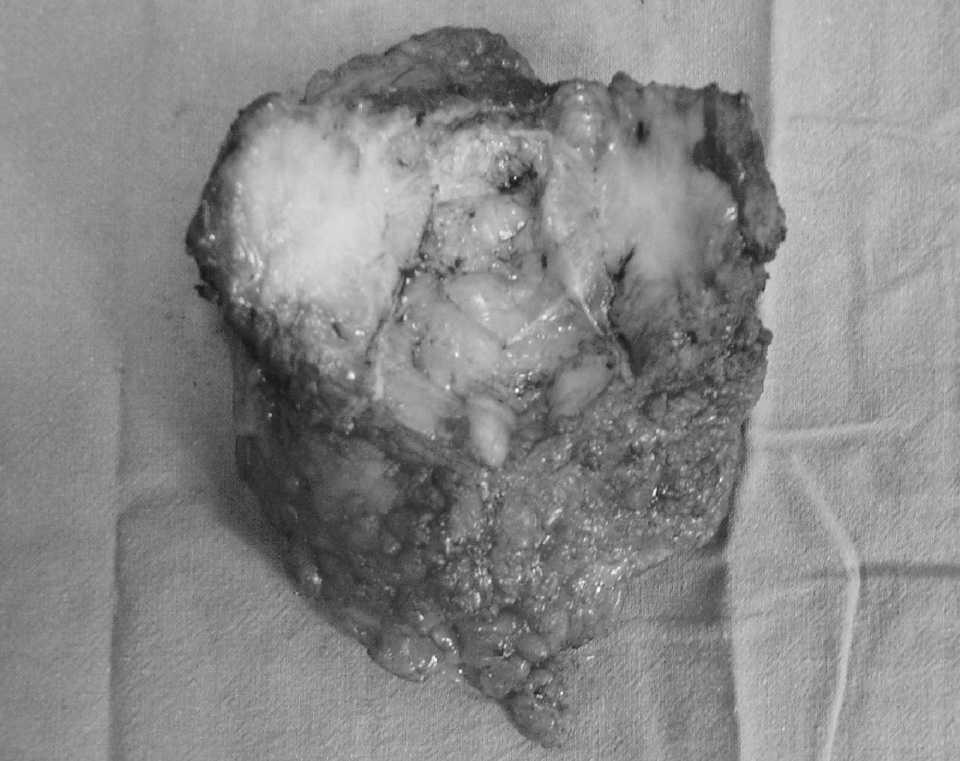

En agosto de 2003, la paciente acudió por molestias en la laparotomía. En la exploración se observaba una tumoración dura y dolorosa a la palpación. Se realizó una TC (fig. 1) en la que se observó un tumor extraperitoneal compatible con recidiva. Se practicó una pun-ción-aspiración con aguja fina, que reveló una metástasis de adenocarcinoma. La TEP mostró una área hipermetabólica en el epigastrio compatible con una recidiva única en la pared abdominal (fig. 2). Se realizó la exéresis de la lesión (fig. 3) y la colocación preperitoneal de malla de polipropileno. El estudio histológico reveló una metástasis de adenocarcinoma con márgenes libres de tumor.